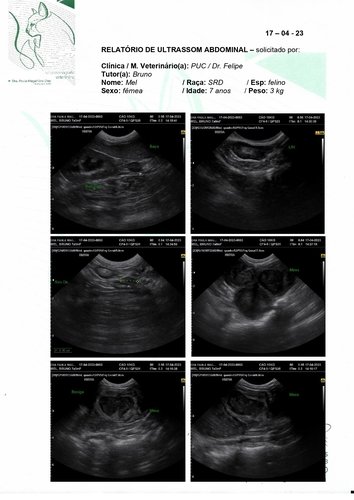

Olá, meu nome é Mel tenho 7 aninhos e peso 3kg (sim, sou bem pequinininha pra minha idade e comparado ao meu irmão de ninhada). Eu e meu maninho Cheetos fomos adotados pelo meu papai Bruno quando nossa antiga tutora faleceu. Nós ja tinhamos 2 aninhos na época, e nunca degrudamos um do outro nesses anos todos. Desde quando meu papai nos acolheu tínhamos que ficar separado da nossa irmã mais velha porque eu sempre fiz meu xixizinho em todo lugar que eu vejo, não faço na caixa de areia e nem mesmo cubro quando decido fazer lá. Mas nunca faltou carinho e amor independente de tudo. Recentemente papai e mamãe decidiram me levar no veterinario para ver o que seria esse problema de xixi em todo lugar, o doutor pediu ultrassom e infelizmente descobrimos a princípio um tumor bem grande perto da bexiga (o qual poderia ter deslocado minha bexiguinha e talvez possa explicar algumas coisas). O doutor disse que teríamos que fazer uma tomografia em outro estado pois onde moramos não tem, e pelas contas dos meus papais ia ficar mais de R$2000,00 fora a cirurgia ><. Mas o doutor disse que podemos ir direto pra cirurgia pra tentar solucionar e não alastrar mais o tumor. Quando chegamos para a cirurgia nao pude fazer por ter fugido do jejum porem me pediram pra refazer os exames e nisso apareceu que o que era um tumor parecia mais uma castração mal feita que tinha deixado partes do ovario e tava causando infecções. Meus papais vieram pedir ajuda pois a cirurgia vai ficar cara fora os medicamentos.

Vamos anexar aqui todas fotos, exame e valor da cirurgia! Qualquer ajuda é bem vinda e contamos com vocês pra logo logo eu ficar bem de novo e poder ficar grudada brincando com meus irmãozinhos!! <3